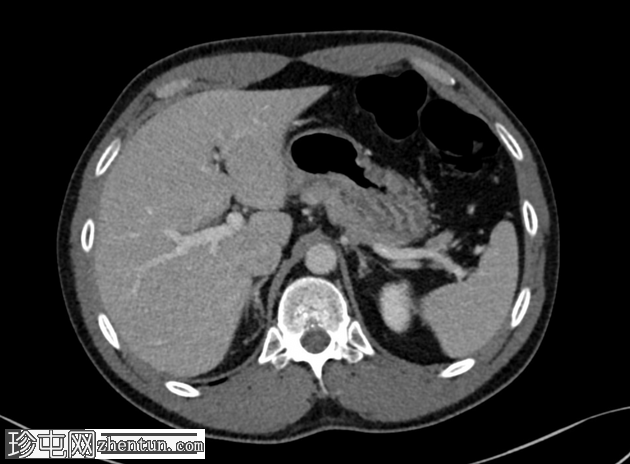

轴位增强扫描(门静脉期)

冠状位增强扫描(门静脉期)

盲肠位于盆腔正中,充满粪便。回盲瓣位于正中。未见明显炎症改变。

CT检查未见明显炎症,实验室检查结果(包括炎症标志物)也证实了这一点。

患者的症状可能与盲肠游离有关。盲肠游离通常无症状,可表现为间歇性下腹痛(盲肠游离综合征),极少数情况下可并发肠扭转。